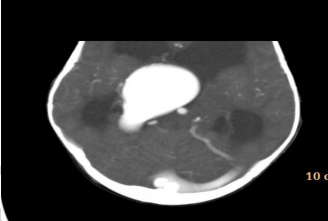

Um lactente de 3 meses de vida é encaminhado para atendimento em razão de aumento do perímetro cefálico (PC). A mãe não havia realizado pré-natal, mas nega uso de substâncias ou processos infecciosos durante a gestação. A criança foi encaminhada para avaliação cardiológica em razão de sopro cardíaco. Ao exame, percebe-se taquipneia leve, PC superior a 2 desvios-padrão, ausência de dismorfismos faciais e fontanela anterior aberta e abaulada. Tônus e trofismo estão preservados, e o paciente eleva os quatro membros contra a gravidade e tem reflexos normoativos. A tomografia de crânio é apresentada na figura. A respeito das informações apresentadas, qual é o diagnóstico para esse paciente?